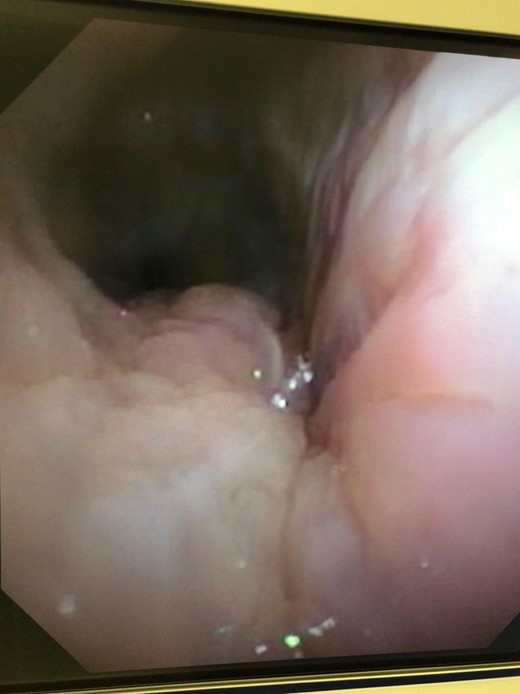

One-year after her original presentation, the patient presented to the emergency room with worsening cough and choking with oral intake. A CT scan of chest revealed a fistula between the right mainstem bronchus and esophagus (Fig. 2A). The patient underwent rigid bronchoscopy revealing a 2-cm defect on the medial wall of the right mainstem bronchus, ~1-cm from the main carina (Fig. 2B). A CT esophagram confirmed extravasation of oral contrast into the tracheobronchial tree (Fig. 3).

(A) CT scan revealing fistula between the right mainstem bronchus and esophagus. (B) Endobronchial view visualizing right mainstem defect.